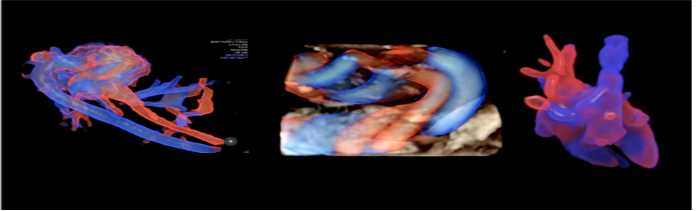

4、9大胎儿核心部位独立成像

E10独有的表面模式、血管模式、组织血管透明模式等智能诊断模式,对胎儿的体表、内脏、血管、骨骼等9大核心部位独立成像,全面弥补传统系统四维彩超在检测范畴及精准度的局限性。

6、胎儿心脏检测评估领域的技术领导者

孕中期胎儿心脏一直是产前筛查工作中的重难项目,所以胎心检查对于超声图像质量及辅助的诊断工具要求非常高。E10具备一整套领先的胎心成像技术,支持从胎儿心脏结构到心功能的全面分析,是胎儿心脏检测评估领域的技术领导。Voluson E10优异的图像分辨率,能更快地展现胎心结构和功能,双平面成像技术可实时观察胎心结构和血流变化,帮助临床医生及时作出准确诊断。